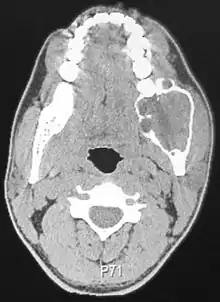

Radiographically, the tumour area appears as a rounded and well-defined lucency in the bone with varying size and features. Numerous cyst-like radiolucent areas can be seen in larger tumours (multi-locular) giving a characteristic "soap bubble" appearance. A single radiolucent area can be seen in smaller tumours (unilocular).[8] The radiodensity of an ameloblastoma is about 30 Hounsfield units, which is about the same as keratocystic odontogenic tumours. However, ameloblastomas show more bone expansion and seldom show high density areas.[14]

Lingual plate expansion is helpful in diagnosing ameloblastoma as cysts rarely do this. Resorption of roots of involved teeth can be seen in some cases, but is not unique to ameloblastoma.[10]